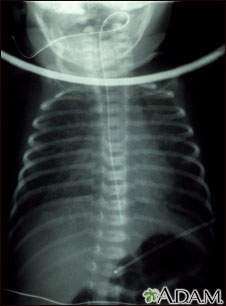

Retorno venoso pulmonar total anómalo, rayos X

El retorno venoso pulmonar anómalo total es un tipo de enfermedad cardíaca congénita. Esta radiografía muestra un aumento de tamaño del corazón, del hígado y de los vasos sanguíneos pulmonares (vascularidad pulmonar).